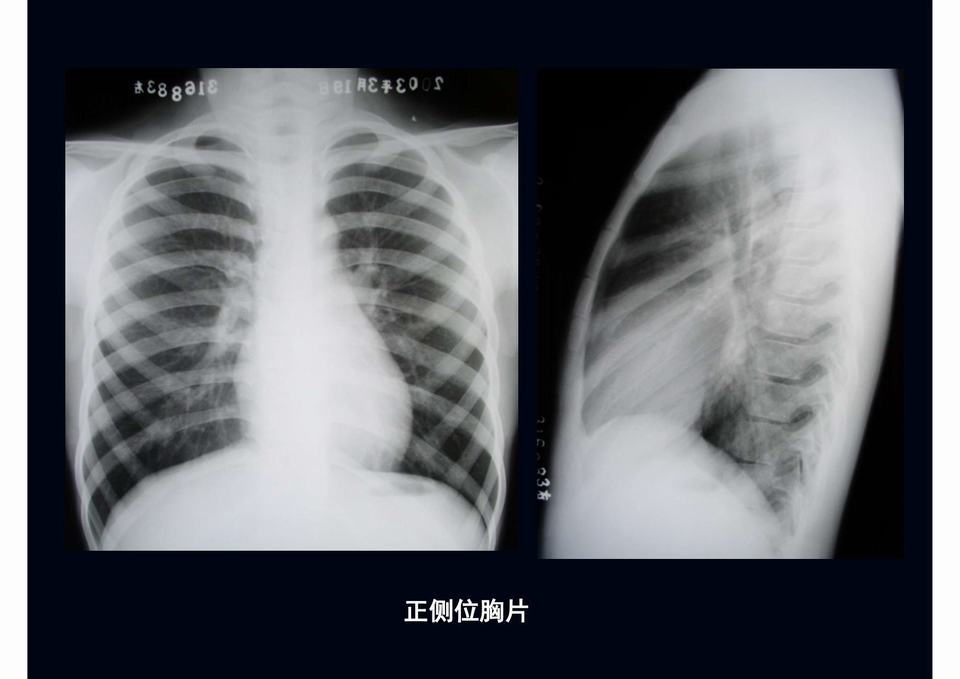

图01